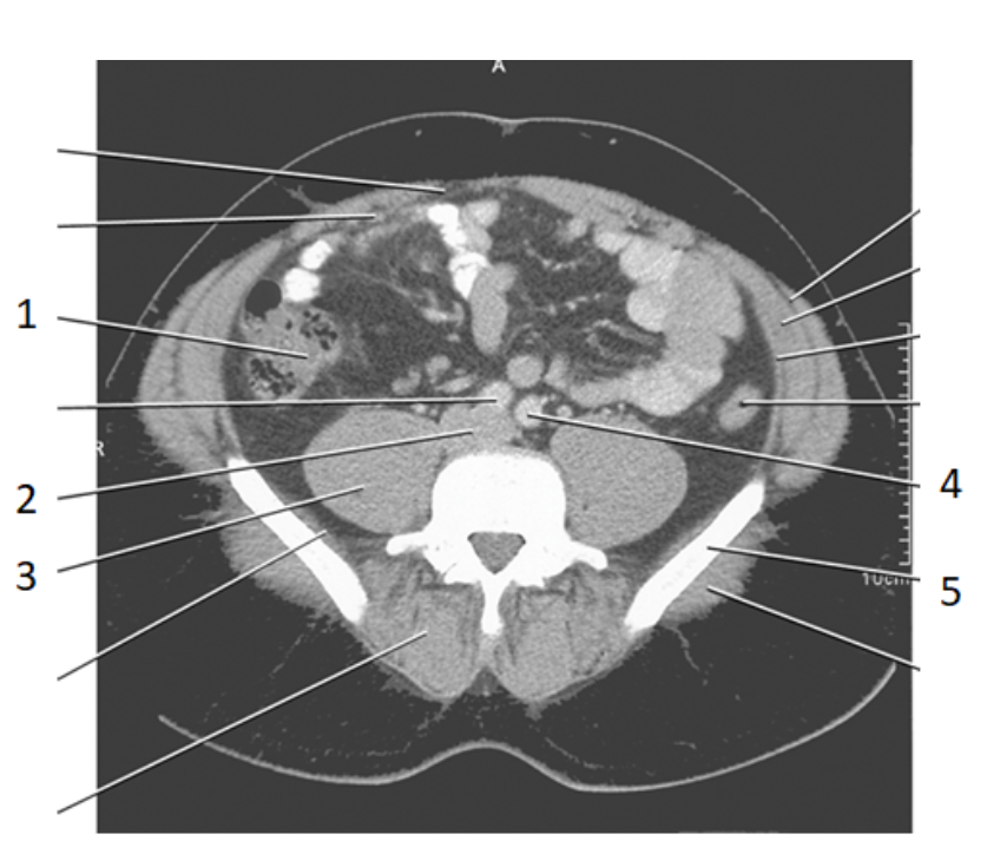

Name | Mastery | Learn | Test | Matching | Spaced | Call with Kai |

2

aorta

6

ilium

4

left common iliac artery

3

ureters

8

psoas